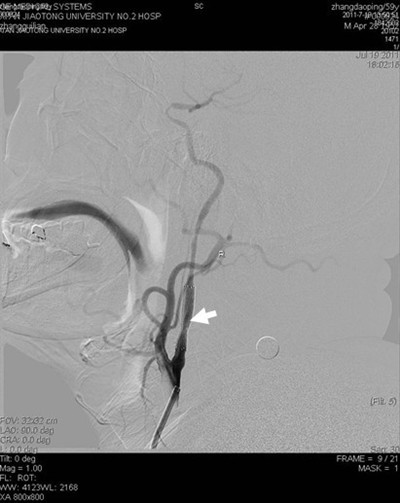

(图2) 闭塞再通血管成形及支架植入后病灶部位显影良好

患者张某,59岁,以左侧肢体活动不灵14天入院,14天前患者突然出现左侧肢体无力,活动受限,并言语含糊,曾于外院就诊,脑CT及MR提示脑梗死,治疗后效果不明显,遂来我院。既往有高血压史数年,长期间断服降压药。入院查体:血压180/100mmHg,左侧口角低,左侧鼻唇沟浅,左侧上下肢瘫痪,肌力III+,左侧肢体共济运动差,左侧巴氏征阳性。余查体未见明显异常。辅助检查:空腹血糖9.8mmol/l。根据患者病史、外院影像学检查,考虑诊断为1.脑梗死(分水岭区);2.高血压病(III级,极高危);3.糖尿病(2型)。为了进一步明确患者脑梗死病因,确定下一步治疗方案,在家属签字同意下,于2011年7月19日进行了全脑血管造影术,术中发现右侧颈内动脉开口处闭塞,但远端血流通过后交通依稀可见,经过我科介入小组缜密讨论,拟给患者行闭塞血管再通手术,经过2小时的紧张手术,取得了很好的手术效果,患者安返病房(见图)。本次手术的成功,是继6月我们对急性闭塞血管进行取栓,我院神经介入工作的又一次突破,在血管闭塞后14天再通,在国内外少见报道,这将快速推动神经介入工作的进一步发展。